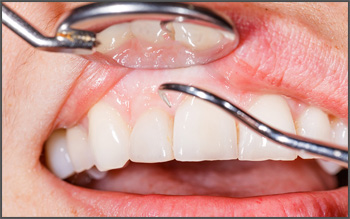

Even with regular and proper brushing and flossing, plaque and tartar will still build up over time. Saliva in our mouths contains calcium and bacteria. Dental plaque is a soft film enveloping teeth which consists of thousands of different types of bacteria embedded in a matrix of proteins, sugars and lipids. Calcified (hardened) dental plaque is known as tartar. Brushing and flossing may remove some plaque but is unable to remove accumulated tartar.

Scaling

Scaling removes plaque and tartar and polishing removes stains and remaining plaque while smoothening and shining teeth so that dental plaque cannot attach easily to tooth surfaces.

Polishing

Polishing may then be followed by a fluoride gel or foam treatment to reduce post-scaling sensitivity and reduce the risk of tooth decay.

Dental scaling and polishing

Dental scaling and polishing is recommended to prevent tooth decay and gum disease, and may be necessary every six months depending on the oral condition of a patient. As infections and diseases can spread from the mouth to the rest of the body, affecting general systemic health, it is important to maintain good oral health and hygiene.

Scaling and Polishing of the teeth, commonly known as tooth cleaning . It is done for the purpose of cleaning of teeth and roots beggings , it involves removing tartar layer and plaque developed on the teeth in the course of time. At Dr. Ehabs Dental Clinic Dubai, it is done by various ways using safe and excellent equipment. We know how important your teeth are for your sound health and your smile.

Gingivitis or periodontal disease begins with bacterial growth in your mouth. If not properly treated, tooth loss due to destruction of the tissue that surrounds your teeth may occur.

In the early stage of gingivitis, bacteria in plaque build up causes inflamed gums and bleeding during tooth brushing. Periodontitis involves the destruction of the supporting structures of teeth where the inner layer of the gum and bone starts to recede from the teeth and form pockets of small spaces, allowing even more bacteria to collect. Infection sets in and bones, gums and connective tissue are destroyed.

Minor Gum Surgery

For patients with deep pockets and gum inflammation, initial non-surgical treatment may not suffice. A minor gum surgery may be performed to remove residual tartar in deep pockets or to reduce it in order to make it easier to keep the area clean. If periodontitis destroyed bone or gum tissue, a bone or tissue graft or special material may be recommended to replace or encourage new bone or gum tissue to grow.